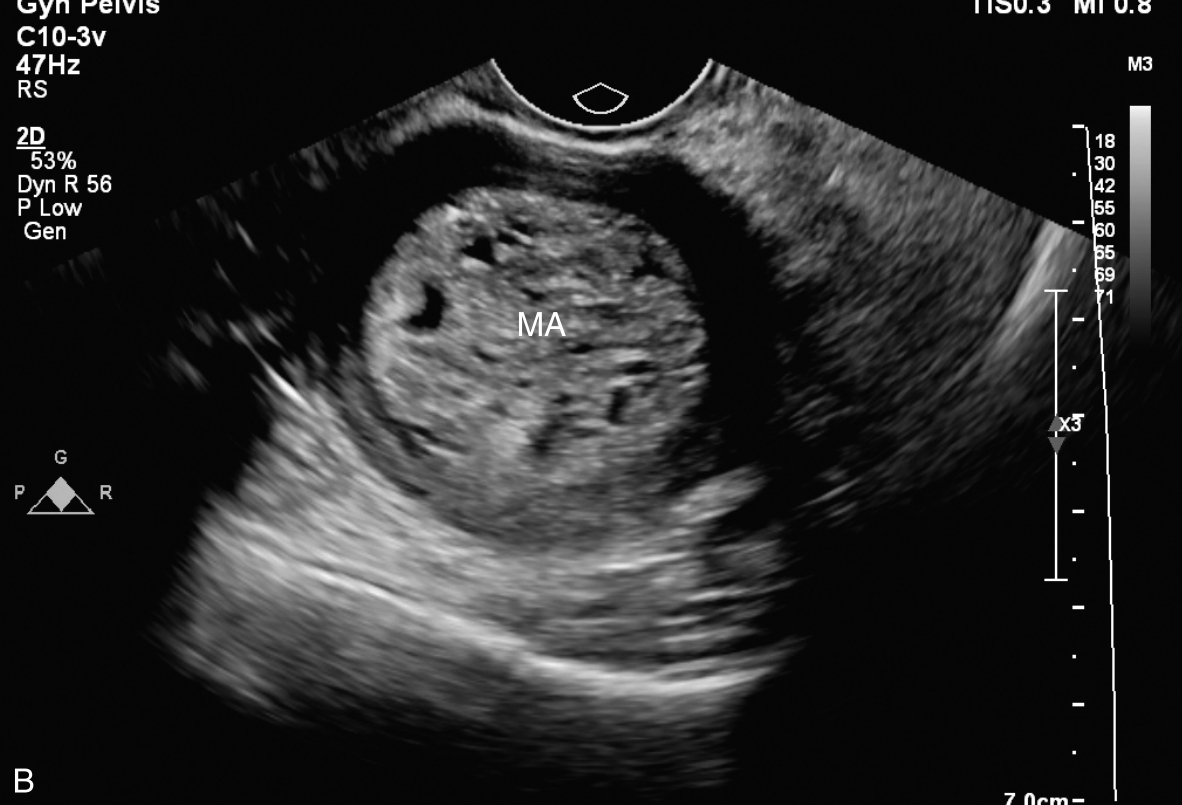

经阴道超声检查见图3-10-1。子宫前位,宫体大小5.6cm×6.9cm×6.5cm,宫腔内查见7.1cm×2.6cm×3.5cm不均质稍强回声,其内回声极不均匀,其内可见多个无回声区,最大无回声区的最大径为0.8cm,周边及其内探及丰富血流信号,该团块与子宫前壁关系密切。宫颈后唇查见囊性占位,大小为2.5cm×1.3cm×1.9cm,囊液清亮,未探及明显血流信号。双附件区未见确切占位。超声检查结果:宫腔内占位,宫颈后唇囊性占位。

图3-10-1 常规超声声像图

A.子宫矢状切面显示宫腔内稍强回声;B.子宫横断面显示宫腔内强回声;C.子宫矢状切面显示宫颈管内占位;D.宫颈管内占位的血流情况;E.宫腔占位的血流情况;F.宫颈囊性占位(箭头所示)。UT:子宫;C:宫颈;MA:肿物。